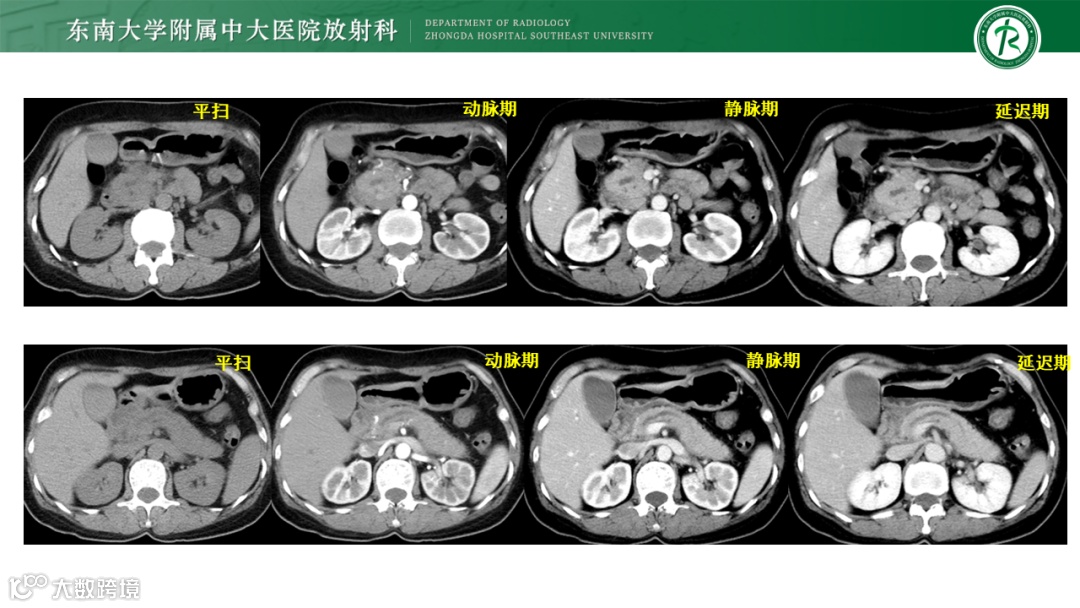

病例1:胰腺导管腺癌-高中分化

病例2:1)炎性肌纤维母细胞肿瘤 2)局限性非肿瘤性病变,如IgG4相关性硬化性疾病 3)韧带样纤维瘤病待排

病例3:胰腺导管腺癌

病例4:IgG4自身免疫性胰腺炎